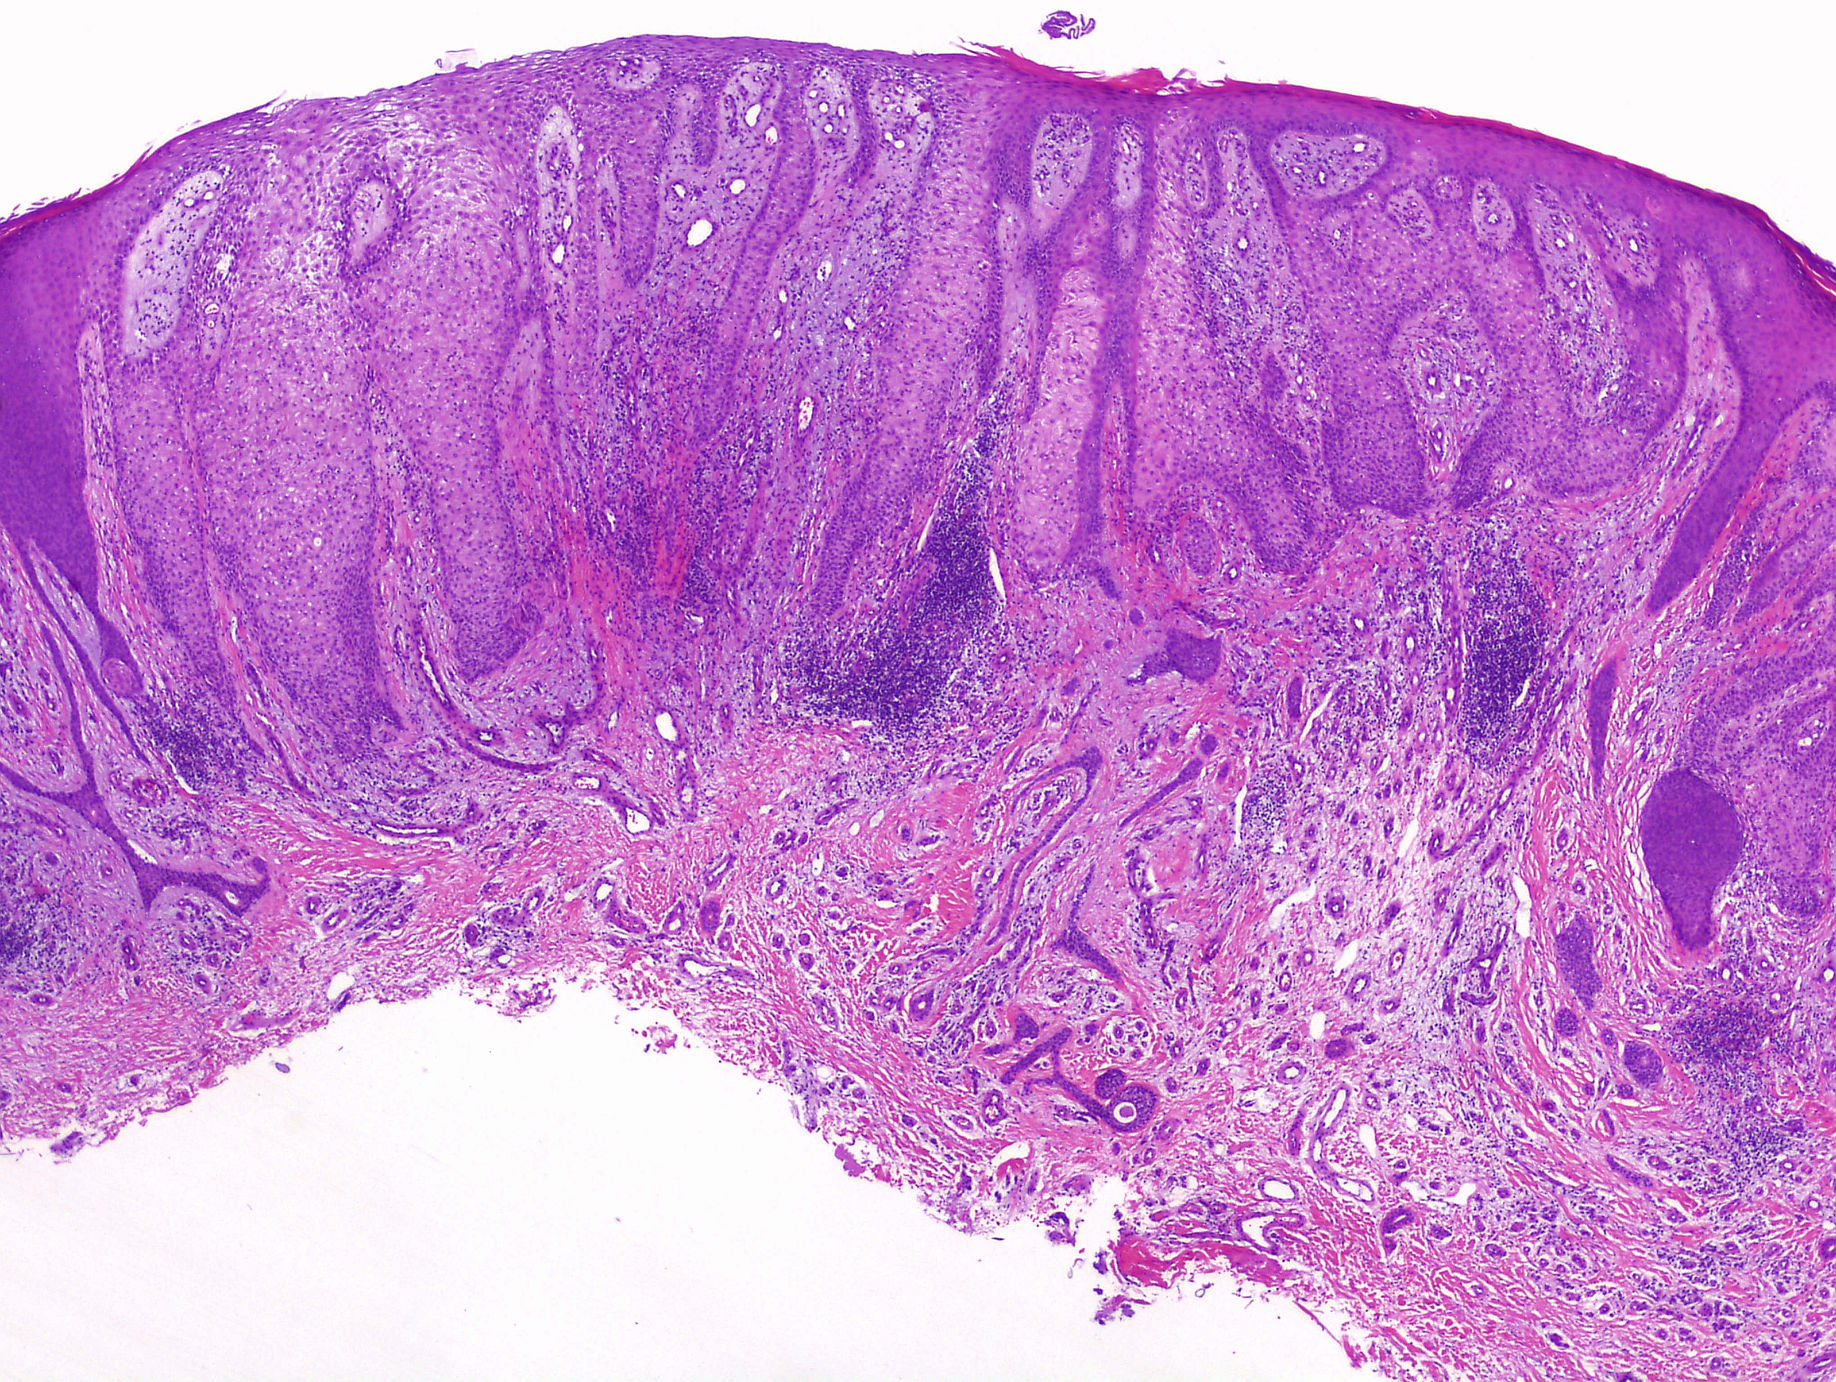

Cas dermatopatologia. Dona de 61 anys amb un àrea hiperqueratòsica vulvar

Març 2013

La biòpsia mostra una proliferació intraepitelial de cèl·lules de nuclis hipercromàtics i citoplasmes clars i abundants. A la porció més basal de dermis es disposen en grups, mentre que a dermis alta apareixen aïllades i són visibles fins i tot a la capa còrnia.